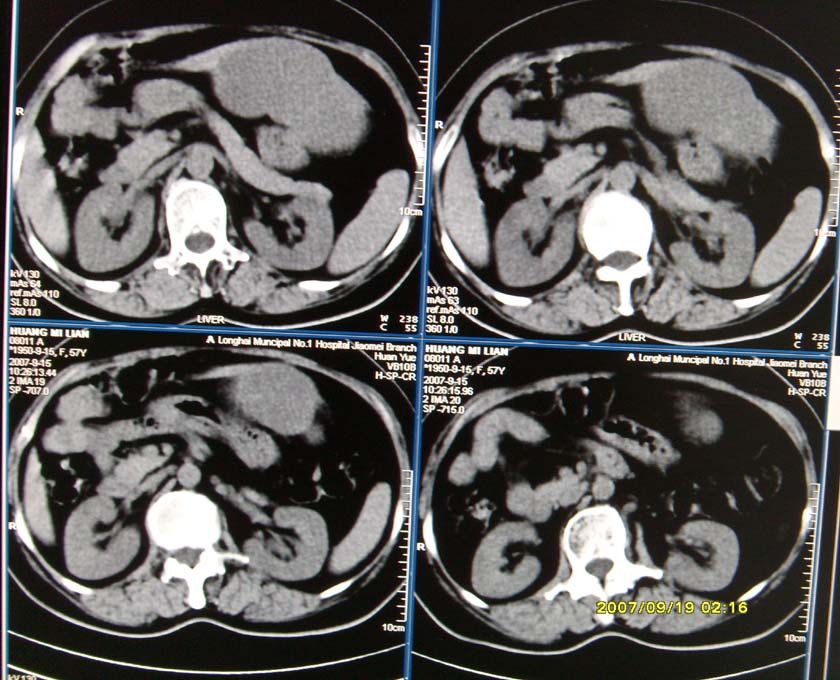

以下是引用逸风在2007-9-19 20:11:00的发言:[br]定位在肝左叶应该没有问题![br]ct显示肝左叶巨大低密度病灶,ct值30hu,密度欠均匀,里面似可见更低密度区;肝门及腹膜后未见明确肿大淋巴结.其与胃之间脂肪间隙存在;彩超提示病灶多发.[br]我个人觉得首先应该增强扫描,从平扫所见结合超声,首先应该考虑血管瘤.

以下是引用davisxuyong在2007-9-19 16:29:00的发言:[br]肝左叶大片状低密度灶,肝癌待排,建议增强。